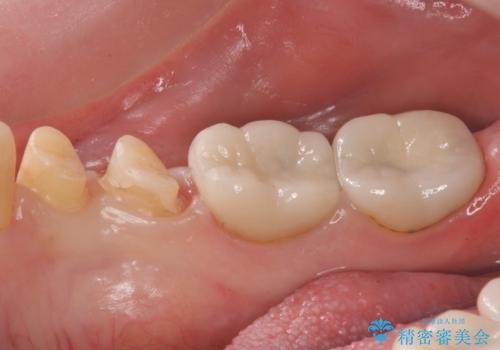

樹脂で継ぎ接ぎになった歯 セラミッククラウンでの治療

- 樹脂の材料の着色が気になるとのことで来院されました。

継ぎ接ぎになっている部分が多かったためクラウンでの治療となりました。